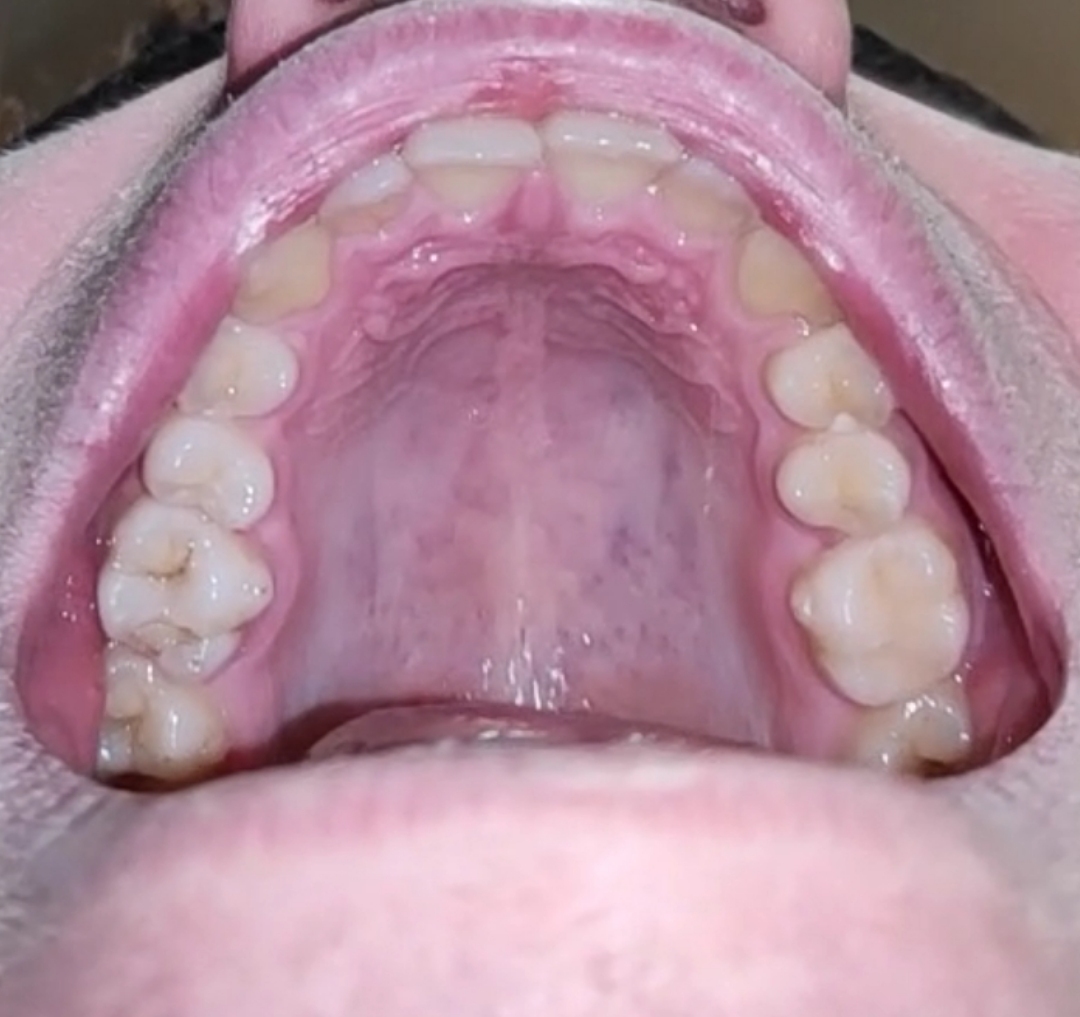

My palette is 35 mm at 15 y.o. Should I Get MARPE?

I can't really tell from this photo, could you take a front-facing photo with your tongue out, looking upwards at the camera? Thanks